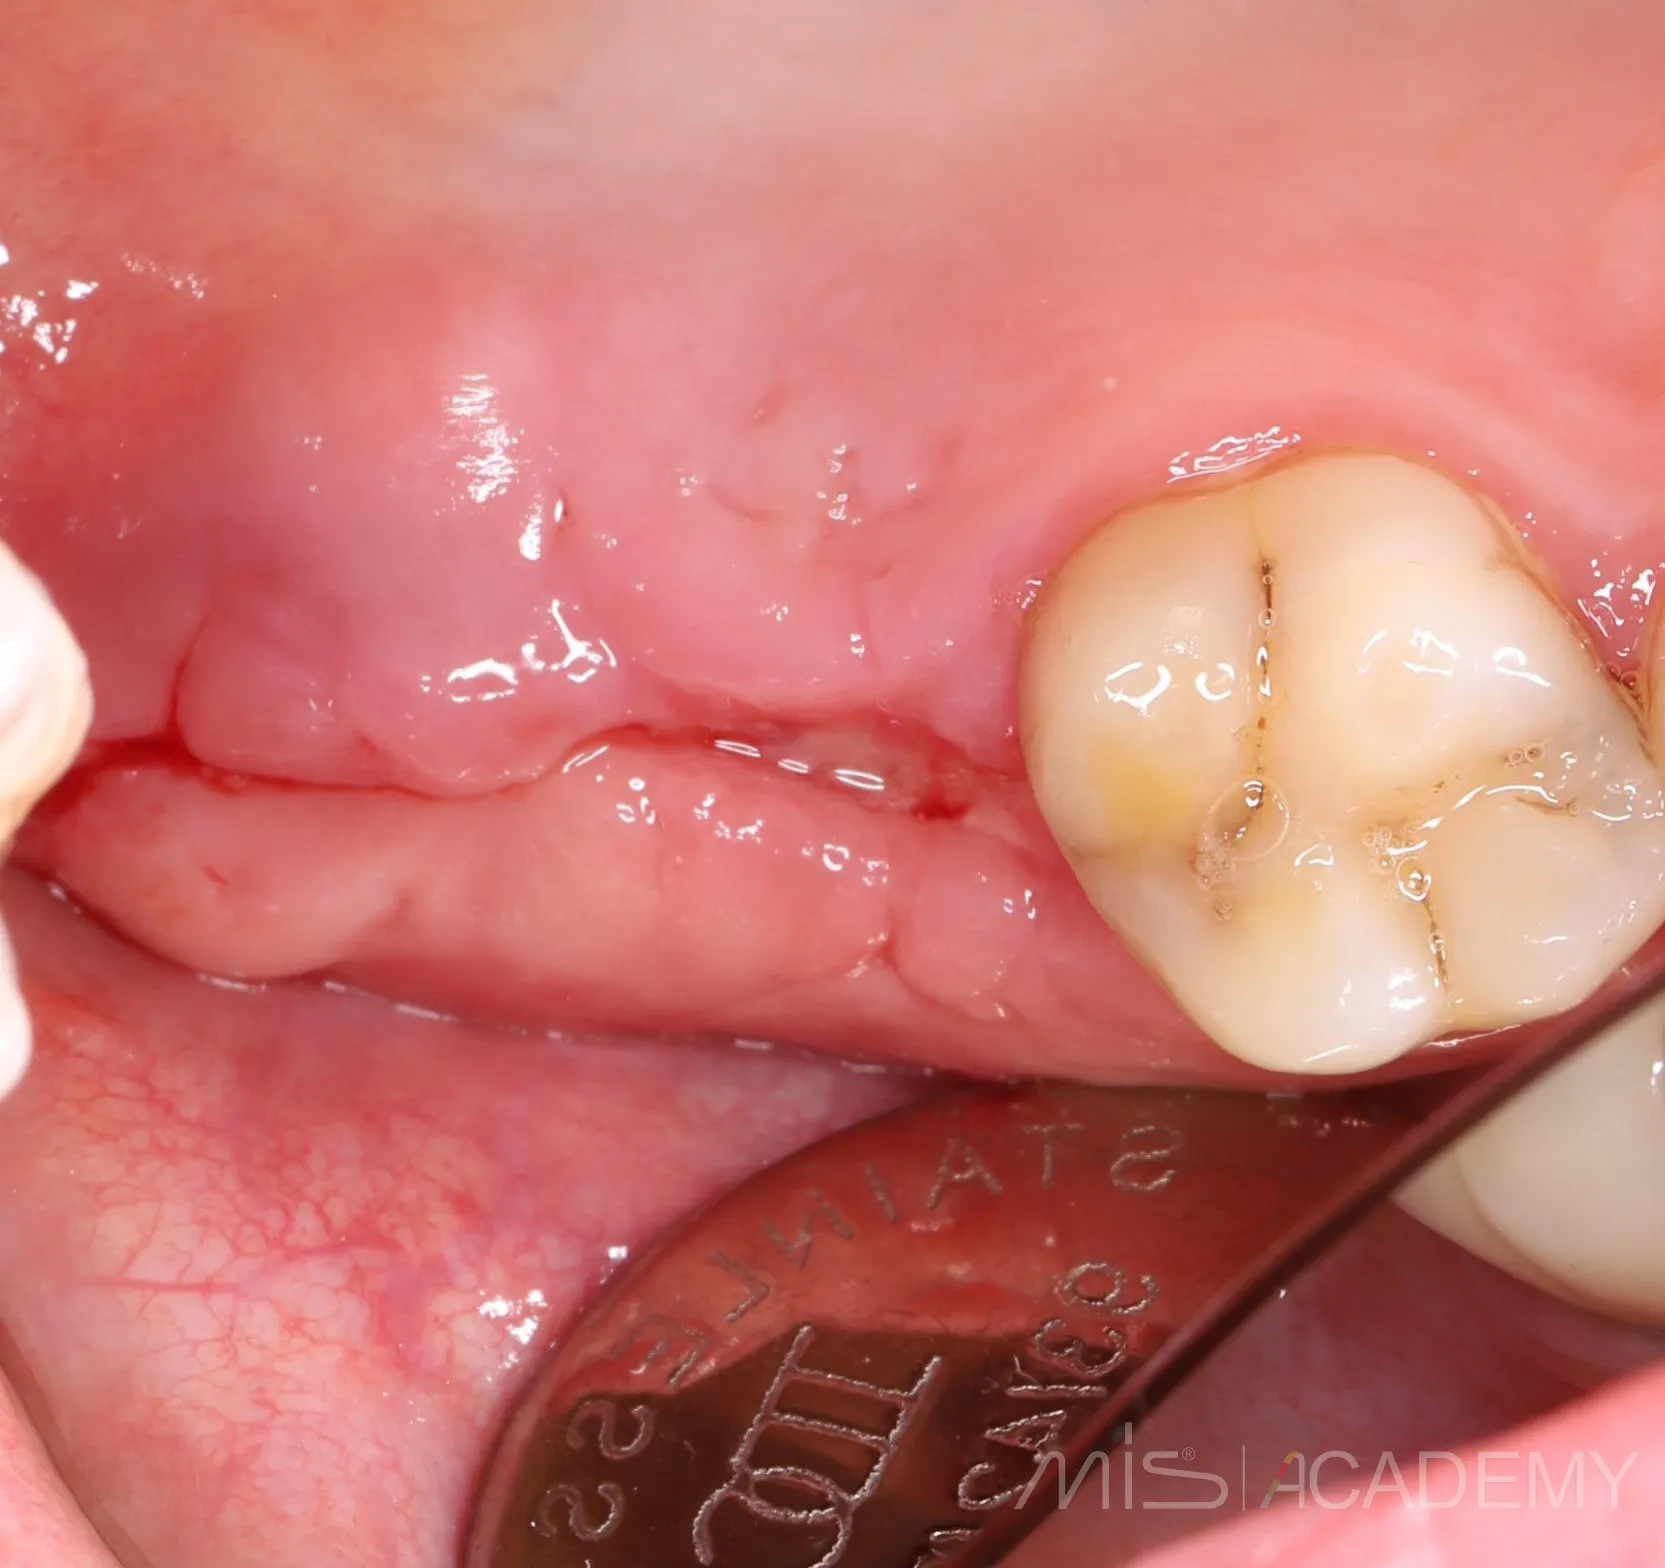

а зона соустья просто попала в кадр. Оказалось, что костный дефект самостоятельно закрылся и теперь там шикарные условия для ОСЛ. Ни разу не видел, чтобы соустья так закрывались. Что ж, будем теперь делать ОСЛ ..